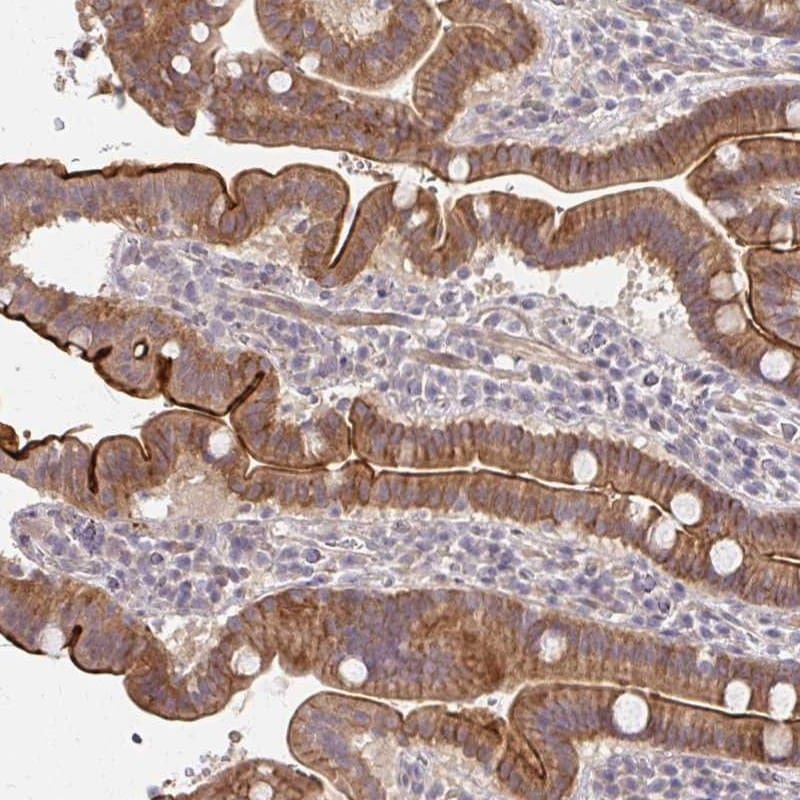

- Immunohistochemical analysis of CXorf40B in human small intestine using CXorf40B Polyclonal Antibody (Product # PA5-63906) shows strong cytoplasmic and membranous positivity in glandular cells.